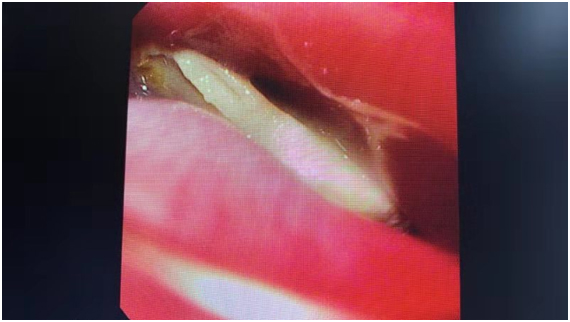

(胃鏡下“元兇”現(xiàn)身)

第二天一早,一夜寢食難安的張女士再次來到仁慈消化內(nèi)鏡室。經(jīng)過麻醉,在胃鏡直視下,潘主任準(zhǔn)確地找到了異物,慢慢將這根在食管壁內(nèi)卡著的雞骨頭順利取出。整個(gè)操作過程中,食管沒有受到任何的拉傷。